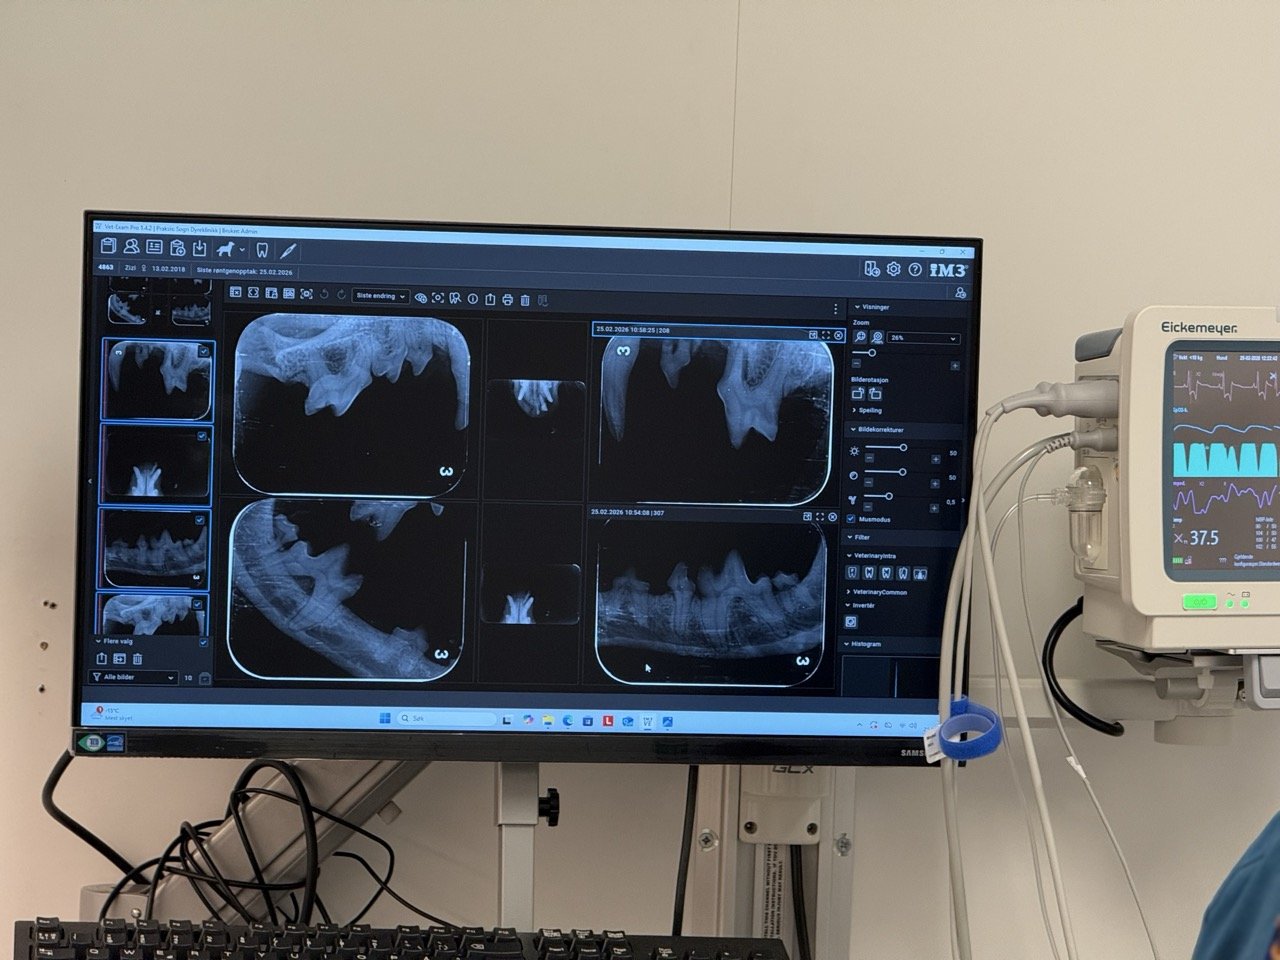

Her på Sogn Dyreklinikk tilbyr vi moderne og grundig tannbehandling av hund, katt, gnagarar og kaninar. Vi nyttar ultralydscaler for skånsam fjerning av tannstein utan å skade emaljen. I tillegg er klinikken utrusta med digital tannrøntgen for at vi skal kunne vurdere heile tanna – også dei delane som ligg skjult under tannkjøtet.

• Tannrøntgen

Alle tannbehandlingar vert utførte i full narkose (gassanestesi), slik at vi kan gjere ei trygg og fullstendig undersøking og behandling utan ubehag for dyret. Vi nyttar fullt overvakingsutstyr som måler pasienten sine vitale verdier – pust, hjarterytme, blodtrykk, oksygenmetning og temperatur. I tillegg får dei intravenøs væskebehandling for å oppretthalde godt blodtrykk.